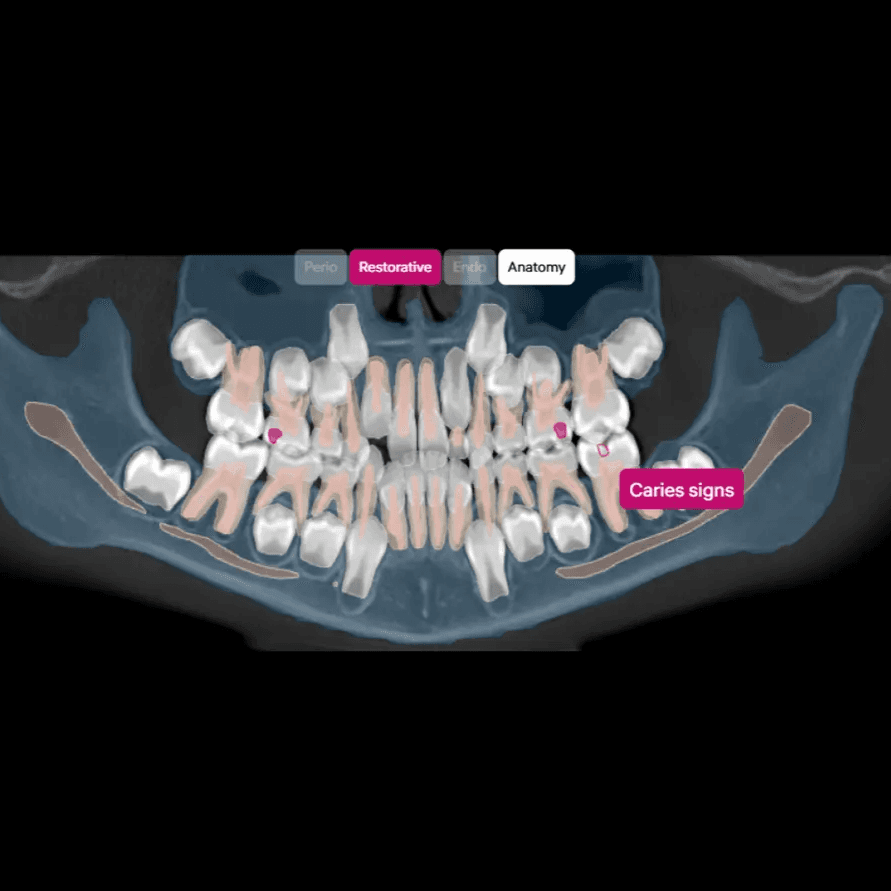

O DxPlan apoia diagnóstico e planeamento com análise por IA de imagiologia dentária 2D/3D, relatórios e visualização por dente — com decisão final sempre do profissional.

Capacidades Principais

Análise 2D/3D (CBCT) com deteção assistida por dente

Deteções assistidas de achados, organizadas por dente.

Relatórios 2D e 3D (CBCT) com medições, etiquetas por categoria e codificação visual

Exportação STL a partir de CBCT (quando aplicável).

Relatório final em PDF para partilha com o paciente